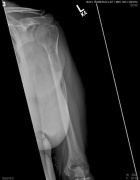

61 year old female with right arm, left hip pain; elevated serum calcium

Zoom image: Radiological image Radiological image.